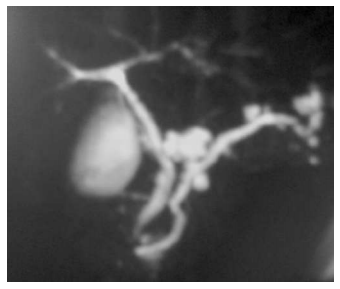

Um paciente de 62 anos de idade, etilista, assintomático, fez exames de ultrassom, que revelaram lesões pancreáticas císticas. Realizou, também, uma colangiopancreatografia, uma ressonância e exames laboratoriais. No exame de sangue, amilase e lipase normais e CEA e Ca19.9 dentro do limite.

A imagem acima corresponde ao exame de